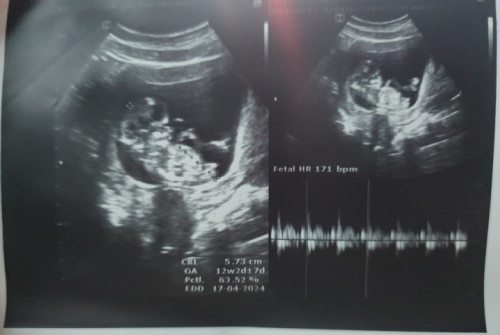

เมษาเหมือนกัน ยังไม่รู้เพศเลย สายสะดือบัง อยากได้ลูกสาวเหมือนแม่จัง

ยินดีด้วยนะคะคุณแม่ บ้านนี้ทีมเมษา67 เหมือนกัน รอผลnifty ค่ะ

ของเราตรวจนิฟค่ะ ตอน 12w เพราะตรวจคัดกรองดาวซินโดรมด้วยค่ะ

ตรวจนิฟ 12w ค่ะ

ตรวจนิฟตอน 12w ค่ะ ตอนนี้ 13w+4d ค่ะ